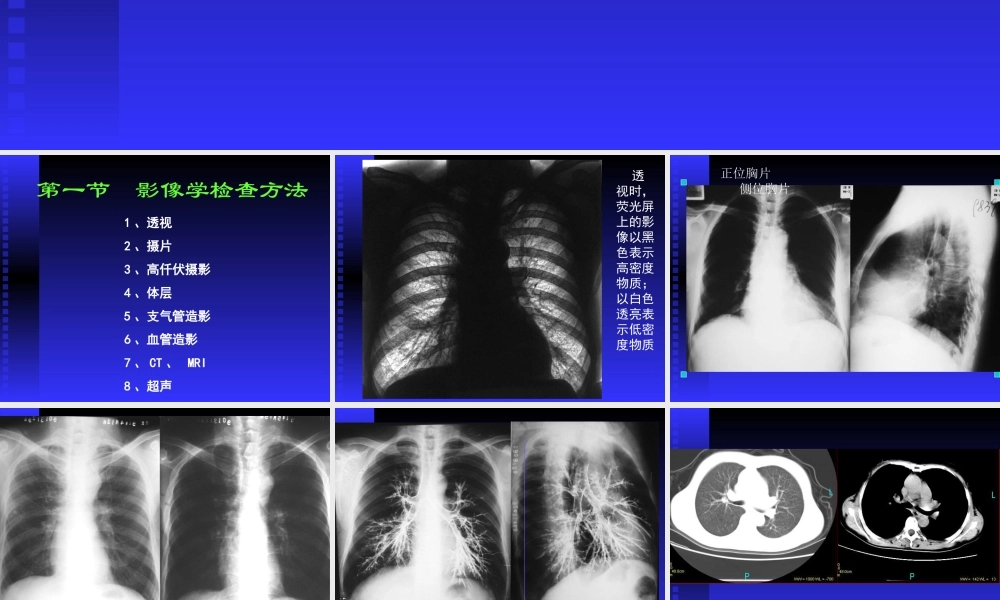

胸部影像诊断学呼吸系统第一节影像学检查方法1、透视2、摄片3、高仟伏摄影4、体层5、支气管造影6、血管造影7、CT、MRI8、超声透视时,荧光屏上的影像以黑色表示高密度物质;以白色透亮表示低密度物质正位胸片侧位胸片高千伏摄影使气管内病变显示(气管癌)支气管造影GUIYANGMEDICALCOLLEGEGUIYANGMEDICALCOLLEGECT用于胸部检查,可根据需要,调节窗宽窗位,显示不同内容第二章正常胸部影像学表现思考重点:能在X线胸片上留下影像的胸壁软组织有哪些?壹胸廓一.胸壁软组织胸锁乳突肌锁骨上皮肤皱折胸大肌乳房和乳头胸锁乳突肌和锁骨上皮肤皱折胸大肌肩胛骨和乳头乳房乳房似肺炎乳房似胸腔积液二.骨性胸廓锁骨胸骨肋骨肩胛骨胸椎胸骨柄勿误为纵隔增宽叉状肋肋骨联合畸形二胸膜水平叶间裂隙斜裂叶间胸膜(细线状致密影)水平叶间胸膜三膈肌位置运动升高或降低原因波浪膈心膈角肋膈角心膈角后肋膈角波浪膈侧肋膈角前肋膈角后肋膈角正常膈肌和各肋膈角、心膈角波浪膈四肺肺叶(肺段、肺小叶、肺腺泡)气管与支气管肺实质肺间质肺野思考重点:解释下列名词:肺实质肺间质肺野肺门肺门角肺纹理一肺实质肺内具有气体交换功能的所有含气腔隙及结构。包括肺泡、肺泡壁、肺泡管和末梢呼吸细支气管影像表现为含气的透亮影二肺间质肺内由纤维结缔组织构成的肺实质的支撑结构和间隙。包括肺泡外壁和肺泡与肺泡之间、肺泡与胸膜之间、肺泡与血管、支气管之间的间隙肺间质一般不留下影像,但可见到在肺间质中走行的肺血管影像显示肺间质和肺实质示意图三肺野胸部影像上,肺部所有表现为透亮影像的部分,包括肺实质和正常的肺间质。两侧肺野透亮度应一致肺野分为:1上野、中野、下野2内带、中带、外带四肺门进出于纵隔与肺之间的各种组织结构肺门的影像主要由肺动脉和肺静脉构成表现为中肺野内带的、粗大的条索状影像肺门角右上肺门和下肺门的血管影像之间形成的夹角左肺动脉弓左肺动脉分出后急剧转向下方,形成的弓状弧形影左侧无肺门角箭头指示肺门角和左肺动脉弓五肺纹理是肺门组织结构进入肺内的延续形成影像的主要是肺动脉分支影像表现为:自肺门向肺野呈放射分布的干树枝状影肺纹理肺纹理:自肺门向肺野呈干树枝样分布的条索状影像,至外带基本消失。粗细多少因个体差异而明显不同CT图像上肺纹理仍为干树枝样条索状密影五纵隔位于两肺之间、胸骨之后、胸椎之前。其内包含心脏、主动脉、气管、主支气管、食管、神经组织、淋巴、脂肪、结缔组织等正位胸片上位置...